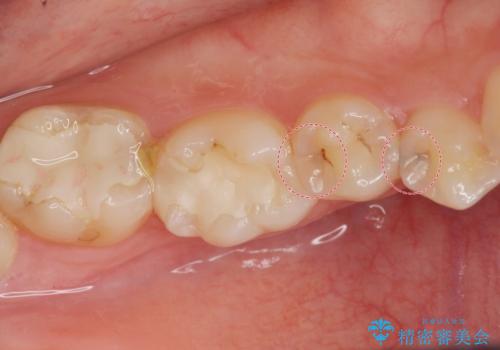

- 奥歯の樹脂の色が気になるとのことで来院されました。

変色しない材料での治療をご希望されたためセラミックインレーでの治療をしていくこととなりました。

継ぎ接ぎになった樹脂の詰め物から一塊のセラミックインレーに置き換えることで着色や二次う蝕のリスクを抑えます。